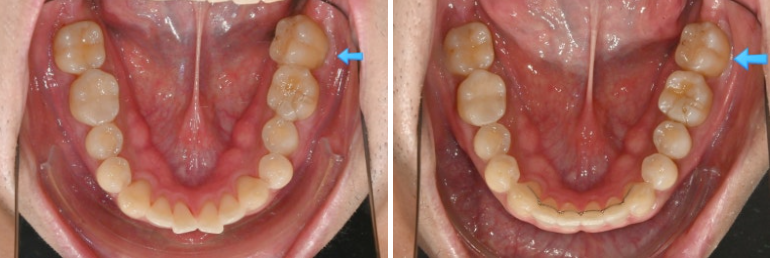

정확히 일치하는 중심선이 눈에 띕니다.

과개교합은 개선되어 이제 아래 앞니가 절반 이상 보입니다.

어금니 교합은 물샐틈 없는 1급 교합관계를 보입니다.

이제 전후 볼까요

총 치료기간은 11개월에 재제작 1회 입니다.

앞니 사이 벌어진 공간은 없어졌고 다시 벌어지지 않도록 고정식 철사 유지장치로 단단히 고정되었습니다

쓰러진 큰어금니가 잘 섰습니다.

가위교합의 개선으로 서로 엇갈려 물리지 못하던 큰어금니가 이제 잘 교합이 됩니다.